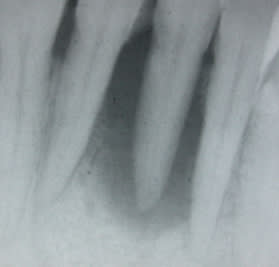

resultat a 1mois, fremissement...

cicatrisation à 6 mois